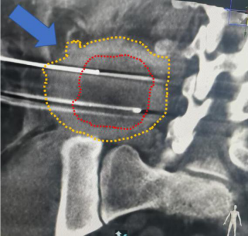

近日,南方医院创伤骨科骨软组织肿瘤亚专业组与介入科通力合作,成功完成了该院首例经皮微创硬纤维瘤冷冻消融术。经过术前缜密规划设计,在C臂CT引导下,在局麻下,进行了髂腰部硬纤维瘤的冷冻消融。手术过程顺利,术后影像显示疗效满意,患者隔天即顺利出院。

图2 术后即刻CT:黄色虚线边框示硬纤维瘤,红色虚线示冷冻消融范围及效果